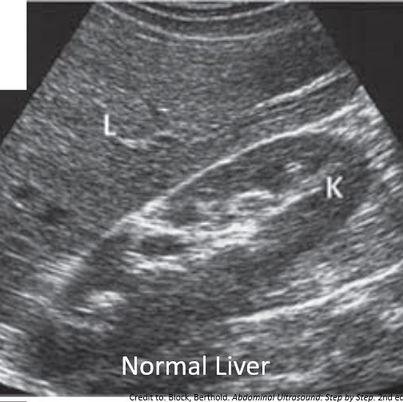

Normal VS Abnormal Appearances